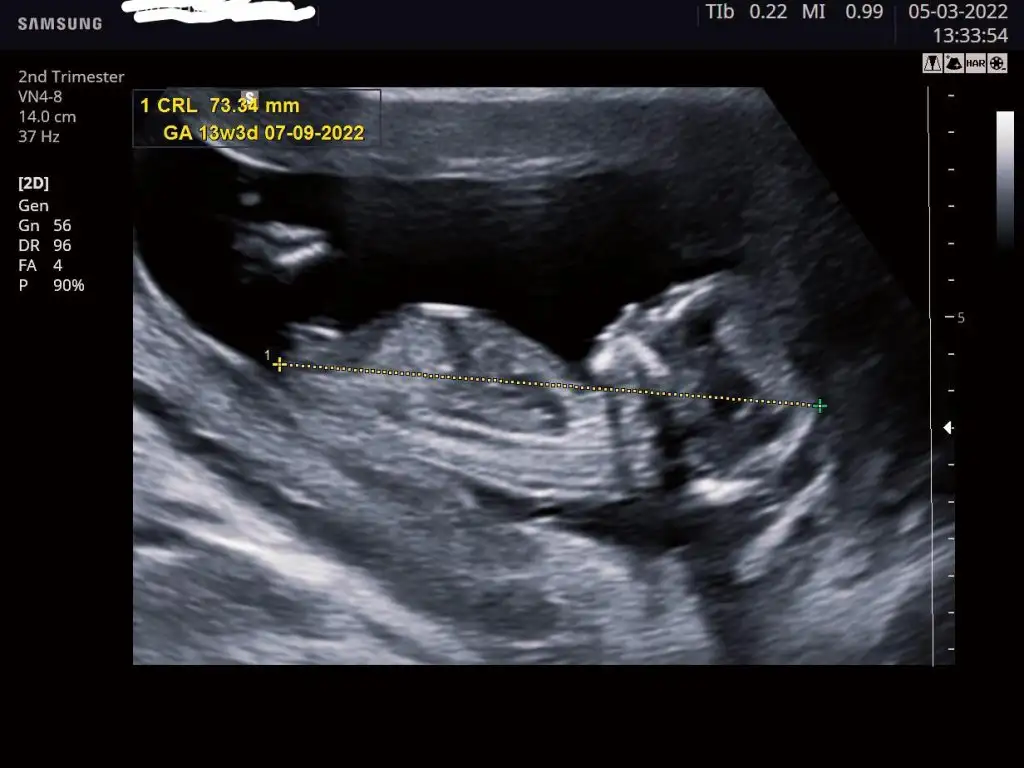

Kontrolden döndük kızlar. Şükür her şey yolunda, 3 gün öne bile geçmişiz. Bugün ikili test ölçümleri yapıldı, ilk denemede o kadar hareketliydi ki görüntü alamadık, ikinci deneme başarılıydı 👍🏻 Cinsiyet konusunu bir sonraki kontrolde netleştirebiliriz dedi. Sizin tahminlerinizi alabiliriz 🐣